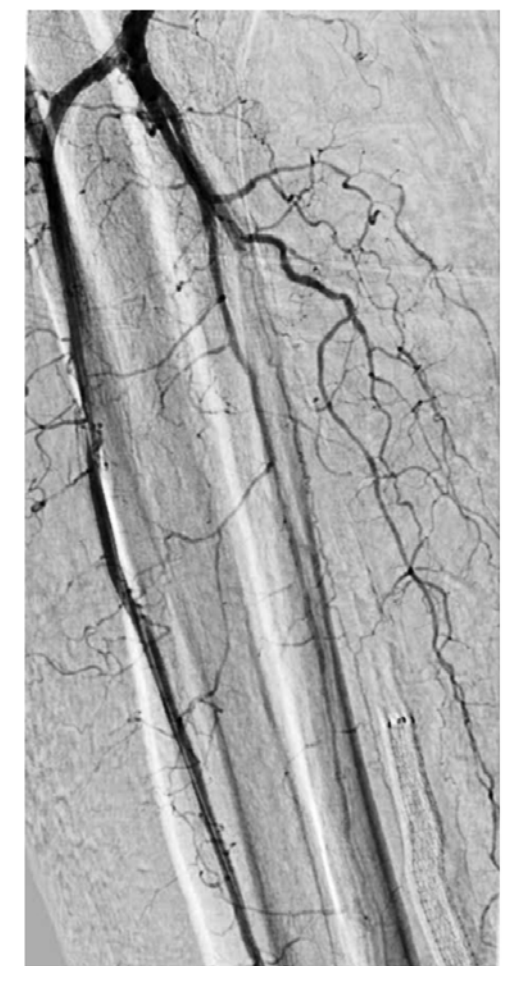

On examination, his right dorsal pedis and posterior tibialis pulses were absent. His right heel had a mature eschar on the posterior aspect with no erythema, drainage, or odor noted in addition to wounds involving his second to fifth digits. Bedside Doppler showed a diminished signal at the dorsal pedis and absent signal at the right posterior tibial. X-ray of the foot demonstrated no evidence of osteomyelitis. His vascular arterial Duplex ultrasound showed an occluded right posterior tibial DVA. The distal anterior tibial artery was severely diseased with a distal occlusion and a monophasic waveform (Figure 1A and 1B). The distal peroneal and posterior tibial arteries were occluded. The plantar veins were studied with ultrasound for possible targets for hybrid DVA using a great saphenous vein to medial marginal vein bypass; however, this was not favored after discussing with vascular surgery. He was evaluated for right below knee amputation which he refused. He was then transferred to our facility to consider other treatment options for revascularization as a last resort. He had a peripheral angiogram that showed a patent distal aorta, iliac arteries, and femoropopliteal segments. The right anterior tibial artery was diffusely diseased with a 90% critical stenosis in its distal segment (Figure 2). The right distal peroneal, posterior tibial arteries and the right posterior DVA were occluded. After careful analysis of the angiogram, we proceeded with an intervention to the anterior tibial artery to establish direct foot perfusion. The left common femoral artery was accessed under ultrasound guidance using a micropuncture needle. A 4F IMA diagnostic catheter and a 0.035 angled Glidewire were used to access the contralateral right common iliac artery. The right SFA and profunda femoral arteries were heavily calcified without severe obstructive disease. The wire was advanced into the right popliteal artery and a 5F by 90 cm Cook Flexor Shuttle was advanced to the origin of the right anterior tibial artery for good support. An Asahi Sion Black 0.014 x 300 cm guidewire was advanced and used to cross the distal anterior tibial stenosis into the dorsal pedis artery. The distal wire was advanced into the first dorsal metatarsal branch after several attempts to wire across the pedal loop. A Corsair Asahi 150 cm microcatheter was then advanced into the dorsal pedis artery and selective foot angiogram was performed. A magnified view of the right foot showed a chronic total occlusion of the dorsal pedis (Figure 3). Laser atherectomy was performed with Philips Turbo Elite 0.9 mm catheter from the origin of the anterior tibial artery to the beginning of the dorsal pedis artery at 80/80 fluency/rate (Figure 4). This was followed by balloon angioplasty with coronary balloons since other balloons will not cross at rated pressure with multiple prolonged 5-minute inflations each of the entire vessel. A Coyote 2.5 x 220 mm balloon was used to further postdilate the anterior tibial artery obtaining excellent angiographic result with improvement of the blood flow into the dorsal pedis as well as the collaterals to the posterior tibial and its plantar branches. The patient’s ischemic rest pain resolved and he was followed linearly along wound care with significant improvement few weeks later.